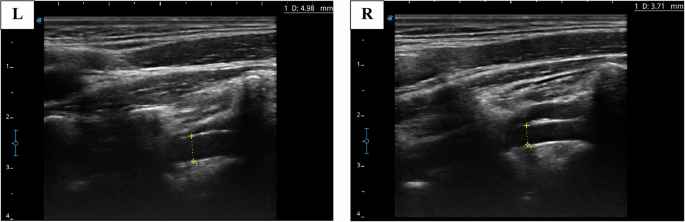

This study employed standardized ultrasound examination protocols to assess the cervical blood vessels, ensuring high-quality imaging and data consistency. Before examination, the participants removed their neck accessories and assumed the supine position to expose and relax the neck region. During the procedure, the participants tilted their heads slightly backward and gently turned them to the contralateral side, ensuring neck muscles relaxation while maintaining a comfortable posture. Ultrasound was performed to assess the bilateral CCAs, ICAs, ECAs, and VAs. Two-dimensional imaging was used to measure the vascular D at specific anatomical sites: 1.0–1.5 cm proximal to the bifurcation of the CCA, 1.0–1.5 cm distal to the ICA origin, 1.0–1.5 cm distal to the ECA origin, and at the V2 segment of the VA, approximately at the same horizontal level as the CCA measurement site. To ensure measurement precision, the images were magnified for clear visualization of the vessel walls and lumen. A VA was considered dominant if its diameter exceeded that of the contralateral VA by at least 0.3 mm54 (Fig. 5). Pulsed wave (PW) Doppler imaging and measurements were conducted at the same locations as those used for the two-dimensional diameter assessments. The beam-vessel angle was adjusted to <60°, with the sampling volume covering the entire lumen and the sampling line positioned at the center of the lumen. PW images were recorded and accompanied by three dynamic video clips (each 2 s long) and saved for analysis. Before analyses, spectral data were preprocessed, including the removal of improperly acquired or noise-affected data. The spectral data sequence was trimmed to generate complete periodic subseries. To improve data quality, sequence averaging and low-pass filtering were employed to reduce noise and eliminate outliers.

The scan shows the bilateral VA diameters in the participant with left VA dominance. VA vertebral artery, L left, R right, D diameter.